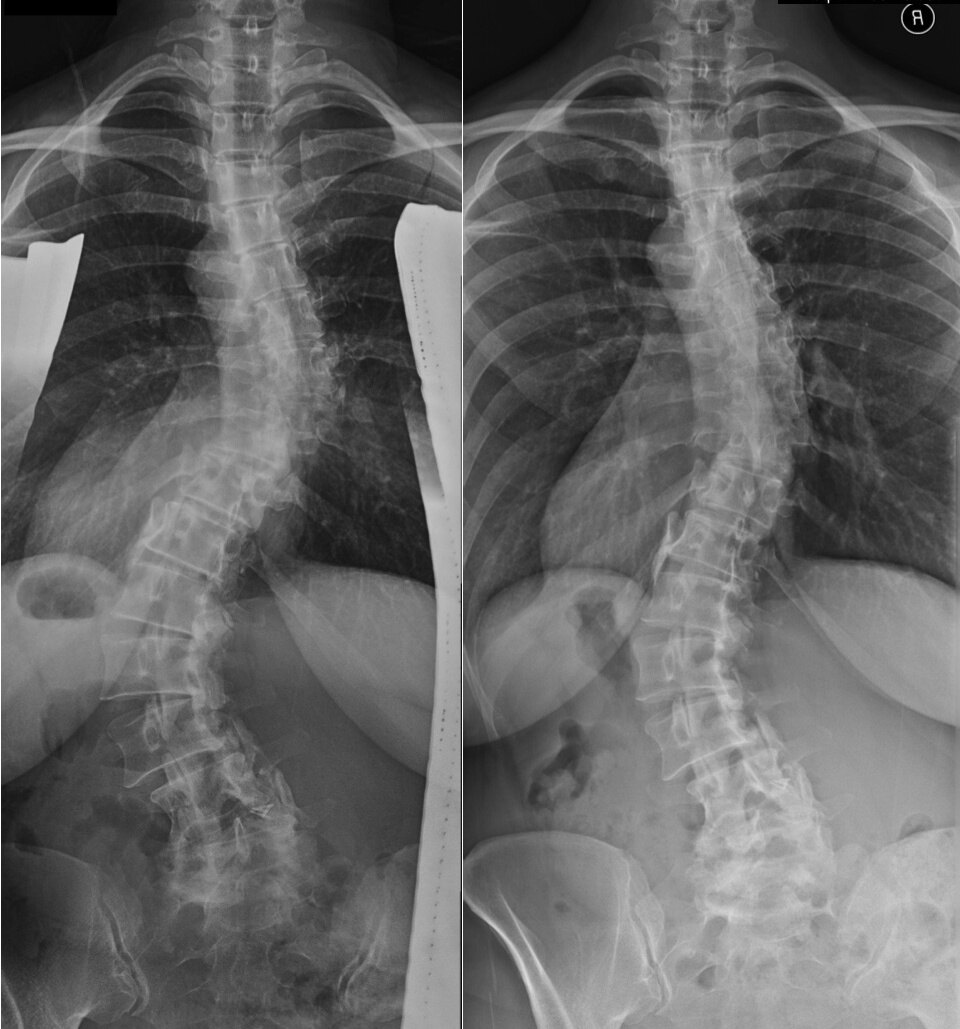

腰椎段脊柱側彎是一種常見的脊柱畸形,運動康復訓練方案可以幫助改善脊柱側彎。以下是制定運動康復訓練方案的一般步驟:評估:首先,需要進行脊柱側彎的評估。可以通過醫(yī)生進行評估,包括身體檢查、X光或MRI等影像學檢查,以了解脊柱側彎的程度和類型。目標設定:根據(jù)評估結果,制定明確的訓練目標。目標可能包括減輕疼痛、改善姿勢、增強脊柱穩(wěn)定性等。練習選擇:選擇適合的運動康復訓練練習。運動康復訓練主要包括呼吸訓練、核心穩(wěn)定性訓練和脊柱伸展訓練等。根據(jù)個體情況和脊柱側彎的類型選擇適合的練習。強度和頻率:確定每個練習的強度和頻率。初始階段可能需要較低的強度和頻率,并逐漸增加。根據(jù)個體狀況和反應調整訓練強度和頻率。個體化調整:根據(jù)個體反應進行調整。監(jiān)測訓練效果,如果出現(xiàn)疼痛或不適,需要及時調整練習內(nèi)容和強度。維持和預防:一旦達到預期的訓練目標,需要繼續(xù)進行維持性訓練,以防止脊柱側彎的復發(fā)。腰椎段脊柱側彎的運動康復訓練可以通過以下具體辦法進行:基礎核心穩(wěn)定性訓練:進行腹直肌、腰背肌和骨盆底肌等核心肌群的訓練,以增強腰部的穩(wěn)定性和支撐力,減輕脊柱側彎的壓力。柔韌性訓練:進行腿部、背部和骨盆的柔韌性訓練,通過拉伸和瑜伽等練習來增加肌肉和關節(jié)的靈活性,改善脊柱側彎的姿勢。強化訓練:進行腹肌、背肌和臀部肌群的強化訓練,以提高腰部的穩(wěn)定性和力量,減少脊柱側彎的程度。姿勢訓練:進行正確的站立、行走和坐姿等姿勢訓練,改善不良姿勢,保持脊柱的正常曲度。呼吸訓練:通過深度和慢速的腹式呼吸練習,加強腹肌和脊柱支撐肌群的協(xié)調性,改善脊柱側彎的姿勢。功能性訓練:進行日常生活中的功能性訓練,如提物、扭轉、彎曲等動作的模擬訓練,增加腰部肌肉的力量和穩(wěn)定性。在訓練過程中,如有疼痛或不適,應及時就醫(yī)。腰椎段脊柱側彎的呼吸訓練可以通過以下方法進行:腹式呼吸:躺在平坦的地面上,放松身體,將手放在腹部。深吸氣時,使腹部向上凸起,吸氣時腹部向下凹陷。慢慢地呼氣,重復進行腹式呼吸練習,以加強腹肌和脊柱支撐肌群的協(xié)調性。側臥呼吸:側臥在床上或地面上,將上手放在腹部,下手放在胸部。深吸氣時,感受腹部向上膨脹,呼氣時腹部向下收縮。重復進行側臥呼吸練習,以加強側軀干的穩(wěn)定性和脊柱側彎的調整。呼吸體位調整:坐在椅子上,背部挺直,放松肩膀和頸部。深吸氣時,將頭部向后仰,感受胸部和腹部的擴張。呼氣時,將頭部放下,感受胸部和腹部的收縮。重復進行呼吸體位調整練習,以改善脊柱側彎姿勢和增強腰部肌肉的穩(wěn)定性。呼吸與姿勢訓練:在站立或坐姿時,進行深度和慢速的腹式呼吸,同時調整姿勢,保持脊柱的正常曲度。通過呼吸和姿勢的協(xié)調練習,促進脊柱側彎的調整和改善。需要注意的是,呼吸訓練應在醫(yī)生或物理治療師的指導下進行,并根據(jù)個體情況進行適當?shù)恼{整。在練習過程中,如果出現(xiàn)疼痛或不適,應及時就醫(yī)。腰椎段脊柱側彎的核心穩(wěn)定訓練可以通過以下方法進行:橋式訓練:平躺在地面上,雙腳腳掌著地,雙手放在身體兩側。用腹部力量將臀部抬起,使腰部離開地面,保持幾秒鐘后放下。重復進行橋式訓練,以加強腹直肌和臀部肌群的力量,提高腰部穩(wěn)定性。平板支撐:俯臥在地面上,將前臂放在地面上,肘關節(jié)與肩關節(jié)成90度角。用腹部和背部肌肉支撐身體,保持身體平行于地面,盡量保持姿勢穩(wěn)定。重復進行平板支撐訓練,以增強腹背肌群的穩(wěn)定性和力量。側平板:側臥在地面上,用一只手臂支撐身體,使身體成一條直線。用腹部和側腰肌肉支撐身體,保持姿勢穩(wěn)定。重復進行側平板訓練,以加強側軀干的穩(wěn)定性和脊柱側彎的調整。腹部訓練:包括仰臥起坐、腹肌收縮等練習,以增強腹直肌的力量,提高腰部的穩(wěn)定性。背部訓練:包括超人練習、仰臥腿部提升,單杠等練習,以增強背部肌肉的力量,提高腰部的支撐力。平衡訓練:包括單腳站立、坐姿平衡球訓練等練習,以提高腰部和骨盆的平衡能力,增強腰部的穩(wěn)定性。需要注意的是,核心穩(wěn)定訓練應在醫(yī)生指導下進行,并根據(jù)個體情況進行適當?shù)恼{整。在練習過程中,如果出現(xiàn)疼痛或不適,應立即停止并咨詢專業(yè)人士的建議。腰椎段脊柱側彎的功能性訓練可以通過以下方法進行:倒立訓練:使用倒立桶、倒立床等設備進行倒立訓練,以減輕脊柱壓力,改善脊柱側彎。腰部扭轉訓練:站立或坐姿,雙手放在腰部,進行腰部扭轉運動。可通過增加扭轉幅度和逐漸增加負荷來逐漸加強訓練。穩(wěn)定性球訓練:使用穩(wěn)定性球進行平衡訓練,如雙腿和雙手同時放在球上,保持平衡。逐漸增加難度和穩(wěn)定性球的大小,以提高腰部穩(wěn)定性和平衡能力。功能性核心訓練:進行一些模擬日常生活動作的訓練,如掃地、拿東西等動作,注重腰部的穩(wěn)定性和動作的協(xié)調性。彈力帶訓練:使用彈力帶進行拉伸和強化訓練,以增加腰部肌肉的柔韌性和力量。步態(tài)訓練:進行步行、跑步、爬樓梯等活動,注重腰部的穩(wěn)定性和脊柱的對稱性。需要注意的是,功能性訓練應在醫(yī)生或物理治療師的指導下進行,并根據(jù)個體情況進行適當?shù)恼{整。在練習過程中,如果出現(xiàn)疼痛或不適,應立即停止并咨詢醫(yī)生建議。?